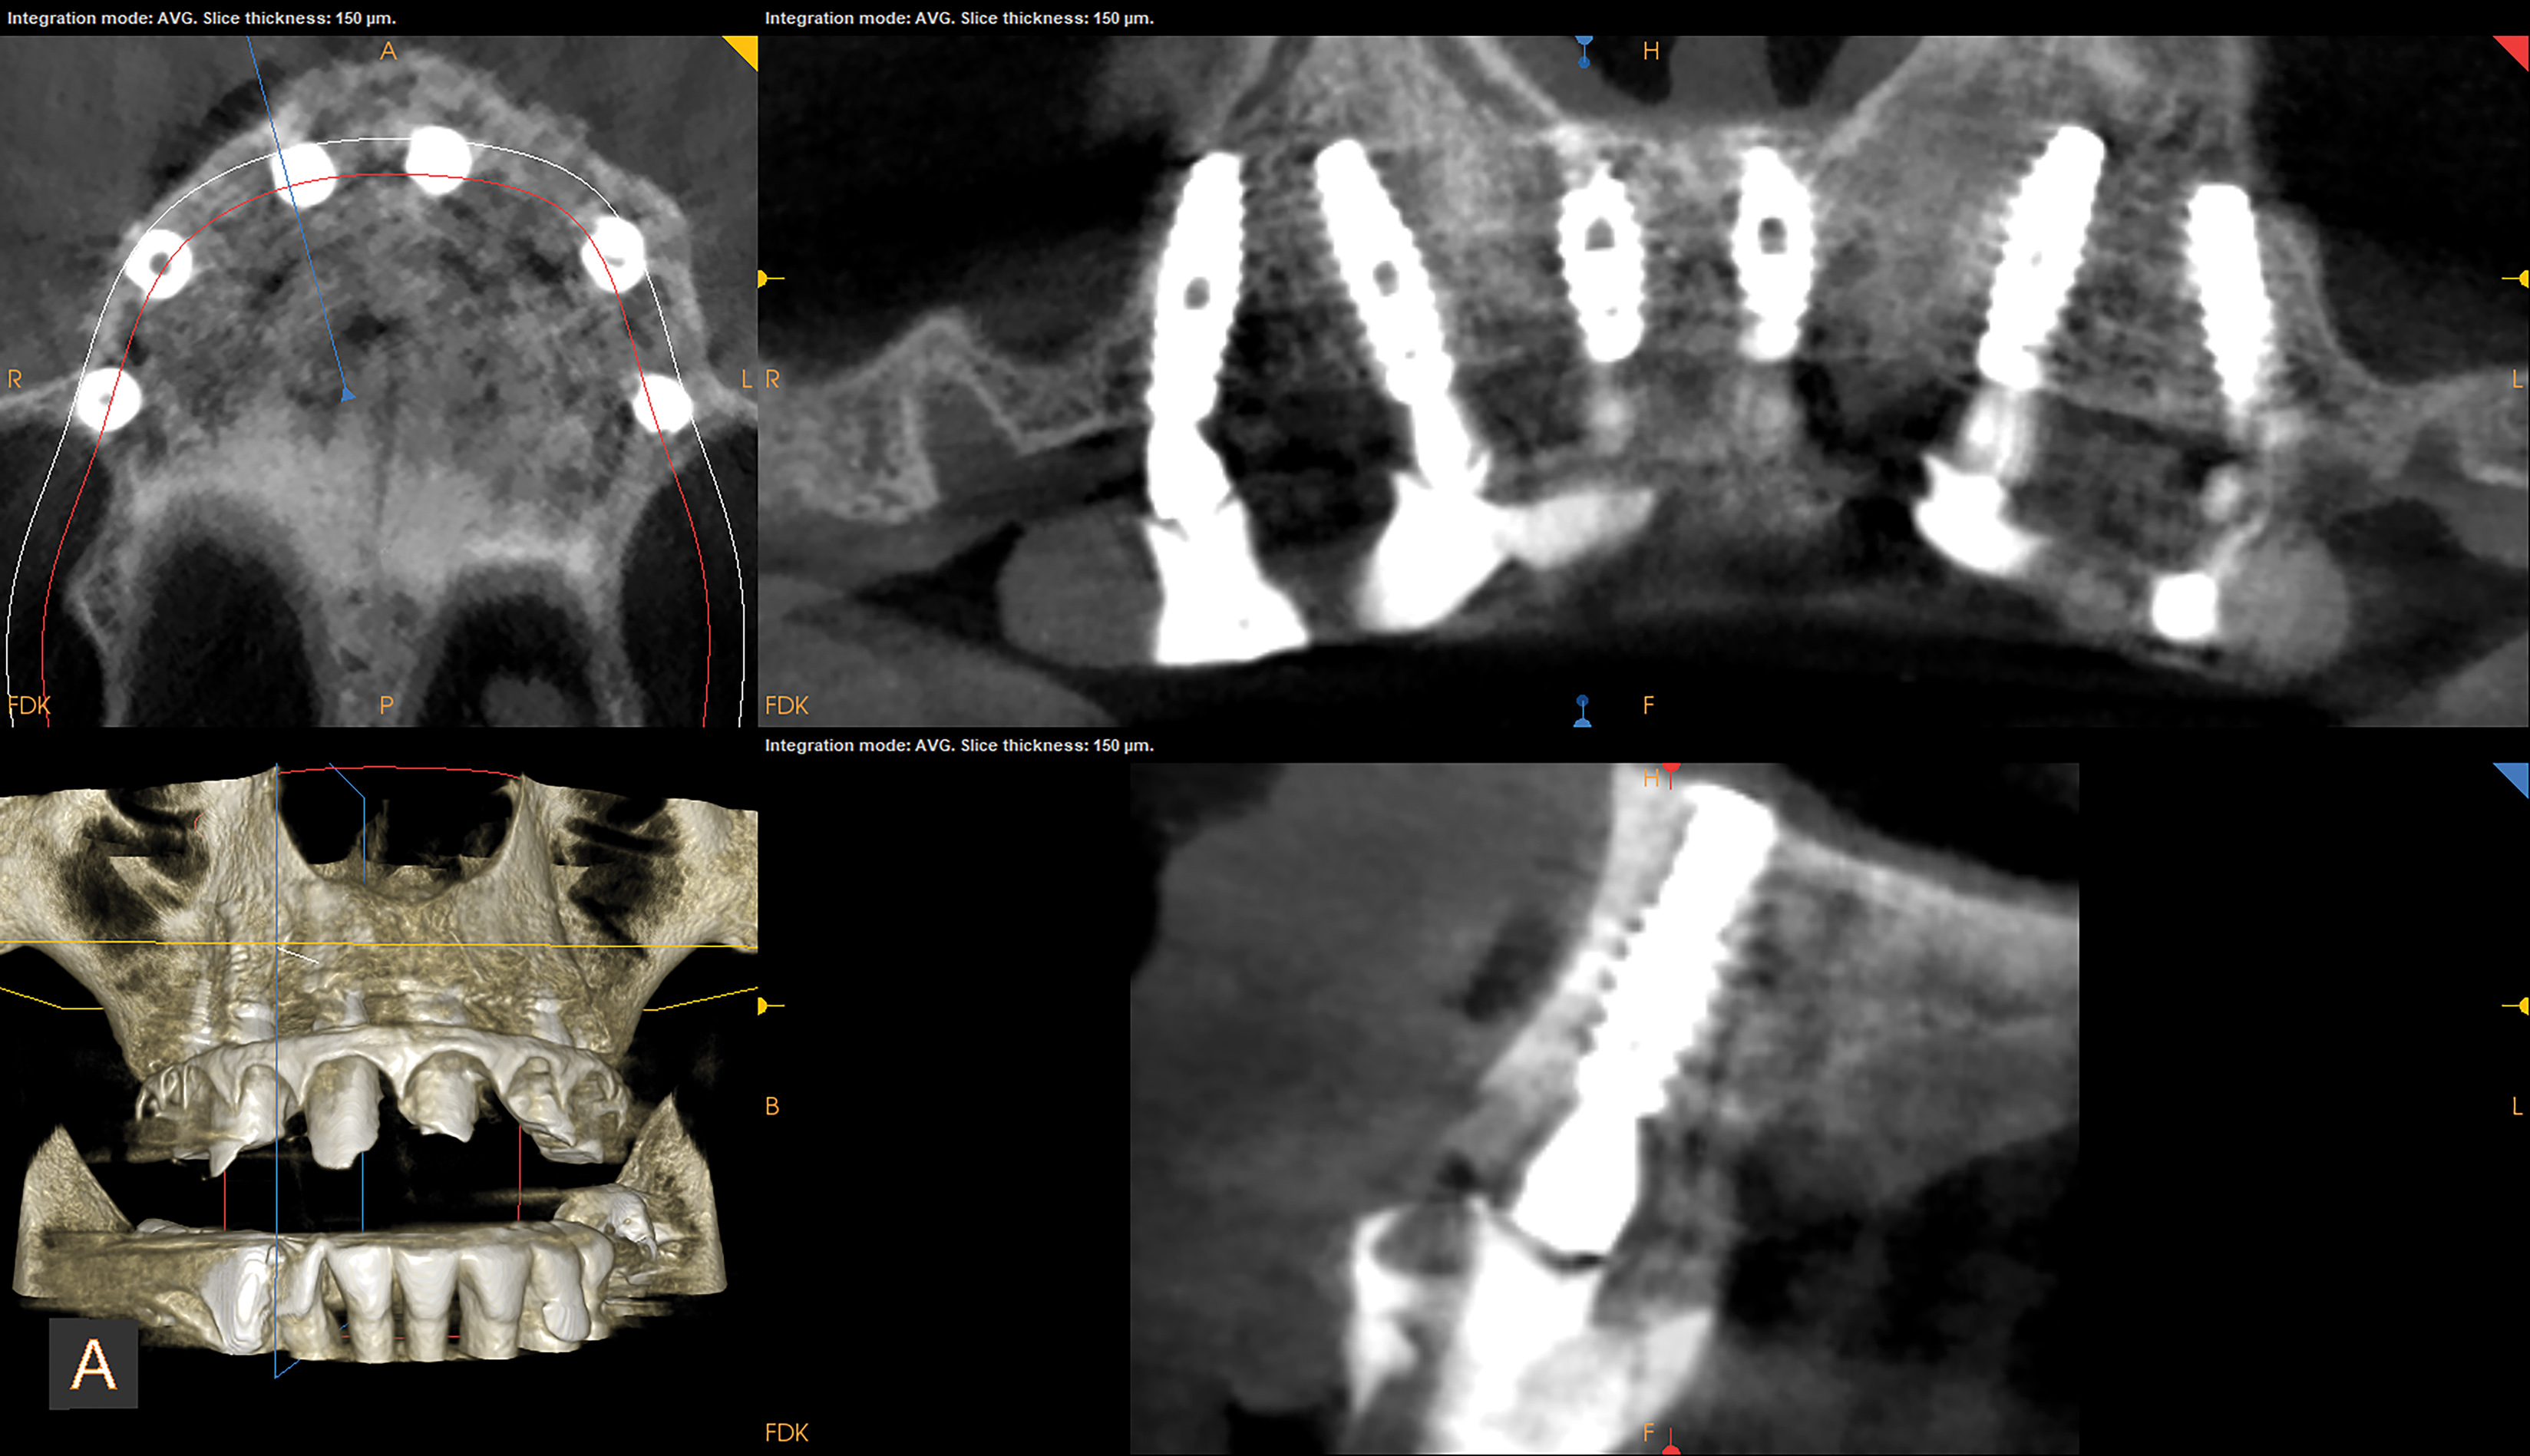

A clinical case of a 76-year-old female patient with a terminal maxillary dentition (Figure 1 and Figure 2) will be used to illustrate this concept of the appliance design mimicking the clinical workflow. The treatment plan for this patient consisted of full-arch extractions, bone reduction, immediate placement of six dental implants, and an immediate fixed provisional restoration. Data acquisition consisted of CBCT imaging a scan appliance (a PVS impression with fiducial markers due to the presence of numerous porcelain-fused-to-metal crowns in the maxillary teeth) in the mouth and a CBCT of the scan appliance by itself. In this case a CS 8100 CBCT system (Carestream Dental, carestreamdental.com) was used. Other comparable CBCT systems include: i3D, Vatech, vatechamerica.com; PreXion 3D Excelsior, PreXion, prexion.com; Planmeca ProMax®, Planmeca, planmeca.com.

Once the data sets were acquired they were imported into implant planning software and merged by matching the fiducial markers. In this case, the implant planning software used was Blue Sky Plan 4 (BlueSkyBio, blueskybio.com). Other comparable implant planning software products include: co-DiagnostiX®, Dental Wings, codiagnostix.com; Simplant, Dentsply Sirona, dentsplysirona.com; 3Shape Implant Studio, 3Shape, 3shape.com. The scan of the scan appliance in the mouth is shown in the upper left quadrant of Figure 3 and the scan of the scan appliance by itself is shown in the lower left quadrant of Figure 3, while the same scan of the scan appliance is shown in the upper right quadrant of Figure 3 with the visibility adjusted to show only the fiducial markers. The lower right quadrant of Figure 3 shows the result of aligning the fiducial markers.

Fig 3. CBCT of scan appliance merge with fiducial markers. Upper left: scan appliance in the mouth with threshold adjusted to show fiducial markers; Lower left: scan appliance by itself; Upper right: scan appliance by itself with threshold adjusted to show only the fiducial markers; Lower right: merged image after matching the fiducial markers in the upper left and upper right quadrants.

Figure 3